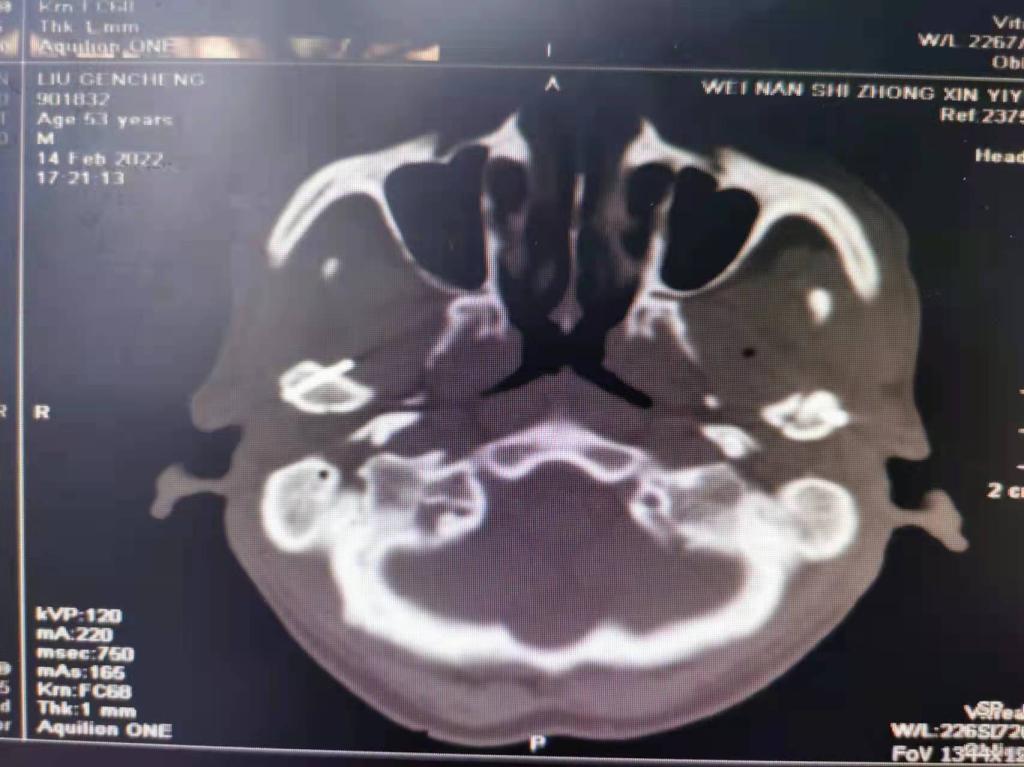

据了解,53岁的患者刘先生在1月25日当天走路不慎摔倒致下颌损伤,造成颏部软组织裂伤和张口困难,前往当地卫生院进行颏部裂伤清创缝合术。术后辗转到乐鱼手机站入口口腔科门诊就诊,并进行颌面部CT检查提示为下颌颏部正中和双侧髁状突骨折,双侧下颌升支高度不一致,右侧较左侧变短1cm,张口重度困难,咬合关系错乱。刘先生因考虑在春节过后再入院治疗,于2月8日再次前来口腔科以“下颌骨骨折”收治人院。

口腔科主治医师蔺非非为患者入院后进行完善术前常规检查和颌间牵引恢复咬合关系。科主任李瑞春结合患者实际病情和检查结果认为,患者的髁突骨折在下颌骨骨折中所占比例较高,约为17.0%-36.3%。髁突骨折时,耳前区有明显的疼痛,局部肿胀、压痛。通过手指深入外耳道或在髁突部触诊,如张口时髁突运动消失,可能有骨折段移位。双侧低位骨折时,2个髁突均被翼外肌拉向前内方,双侧下颌支被拉向上方,可出现后牙早接触,前牙开秴。髁状突骨折易引起下颌后缩,张口困难,咬合关系错乱,关节强直等并发症。考虑患者系陈旧性骨折应尽早实施手术,避免骨折导致的张口困难、关节强直等并发症。因患者已经错过最佳治疗时期,决定尽快为患者进行手术治疗。

科主任李瑞春和主治医师蔺非非经过缜密的术前讨论和充分评估,手术在全身麻醉下进行,术中克服术野狭小操作不便困难,将下颌骨骨折完好对位,顺利地完成了"双侧髁状突和下颌颏部正中骨折切开复位内固定术"。术后检查患者面部对称,双侧下颌升支高度一致,咬合关系已恢复。